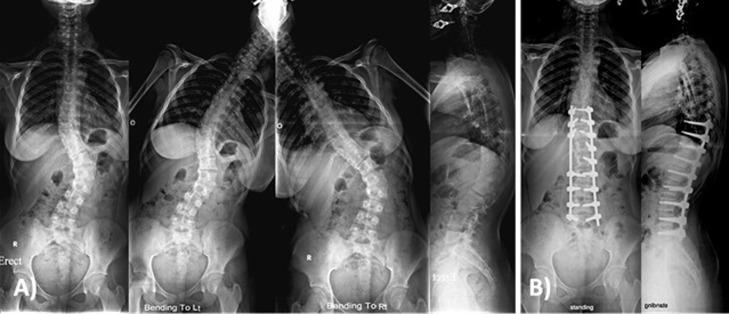

Between 2011 and 2015, all surgically treated patients for AIS were followed up for a minimum of 2 years. Clinical outcomes were evaluated using scoliosis research society-22 (SRS) questionnaire. All patients were classified according to Lenke classification. Major and minor curves Cobb angle as well as sagittal parameters were measured on whole spine X-rays. All patients underwent an intra-operative wake-up test after deformity correction and a minimum of 80% metal density of implants was used.

This study included 50 patients. The mean age at time of surgery was 16.8 years. The mean follow-up period was 38.1 months. The mean correction rate for the coronal Cobb angle of the major curve was 79.12%, while that of the minor curve was 68.9%. The mean thoracic kyphosis angle was 38.4° preoperatively, 29.76° postoperatively and 30.36° at the last follow-up. The mean SRS-22 questionnaire scores improved significantly at the last follow-up (P > 0.001). There were no neurological deficits at the wake-up test. No cases of pseudarthrosis or metal failure were encountered.

2011年至2015年期间,所有接受手术治疗的AIS患者均进行了至少2年的随访。使用脊柱侧凸研究协会-22(SRS)问卷评估临床结果。所有患者均根据Lenke分类进行分类。在全脊柱X射线上测量主弯和次弯的Cobb角以及矢状面参数。所有患者在畸形矫正后均接受术中唤醒试验,并使用植入物金属密度至少为80%的产品。

本研究纳入50例患者。手术时的平均年龄为16.8岁。平均随访期为38.1个月。主弯冠状面Cobb角的平均矫正率为79.12%,次弯为68.9%。术前平均胸椎后凸角为38.4°,术后为29.76°,末次随访时为30.36°。末次随访时SRS-22问卷平均得分显著提高(P>0.001)。唤醒试验时未出现神经功能缺损。未遇到假关节或金属失败病例。